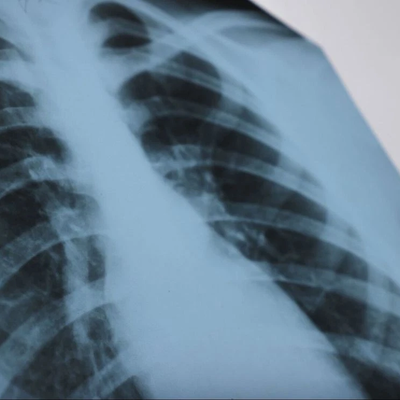

CDC: U.S. tuberculosis cases hit highest level in more than a decade

Tuberculosis cases in the United States have reached their highest in nearly a decade, attributed largely to international travel, but early treatment and prevention are crucial.